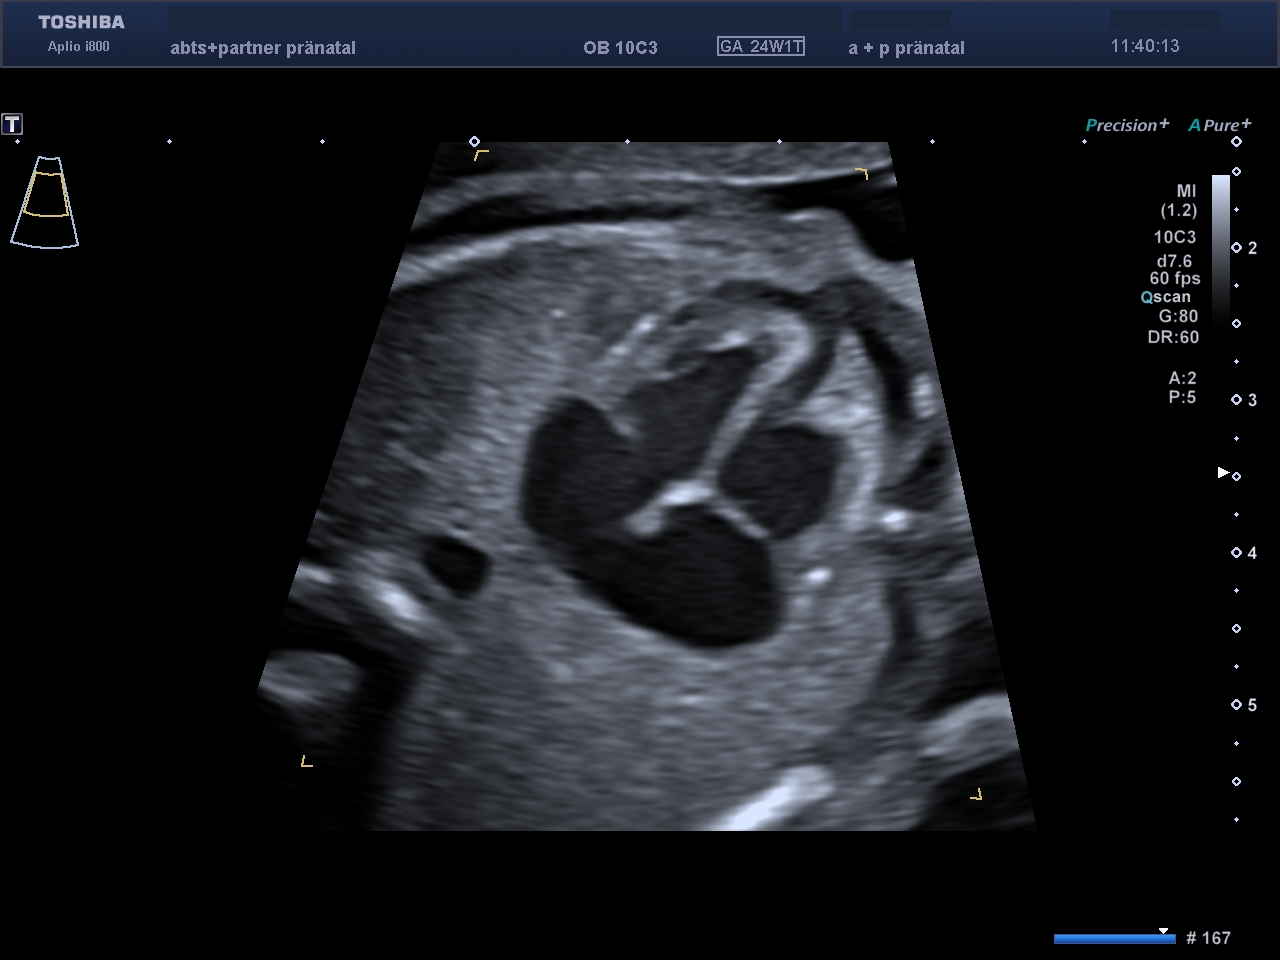

Der kindliche Bauchumfang mit dem gefüllten Magen.

Beide Nieren und Nierenarterien sind vorhanden.